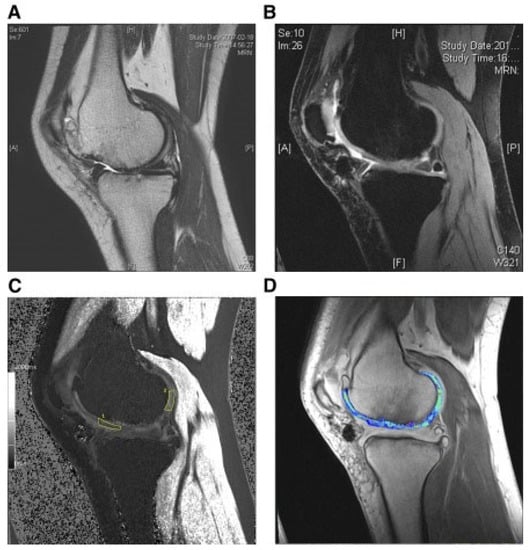

| Park et al. [118] | 2017 | K–L grade III knee osteoarthritis and ICRS grade IV lesions | N = 7; Females = 5; Males = 2; Mean age = 58.7 years | Allogeneic HUCB-MSCs | Surgical implantation of a complex containing stem cells and hyaluronic acid hydrogel (0.5 × 107) | 7 years | Maturing repair tissue was observed at the 12-week arthroscopic examination. The 100 mm VAS and IKDC scores changed from 49.1 and 39.1 to 19.3 and 63.2, respectively, at 24 weeks. |